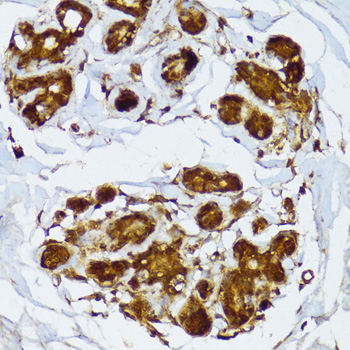

Immunohistochemistry of paraffin-embedded human breast using IRF3 antibody.

Immunohistochemistry of paraffin-embedded human stomach using IRF3 antibody.

Immunohistochemistry of paraffin-embedded human gastric cancer using IRF3 antibody.